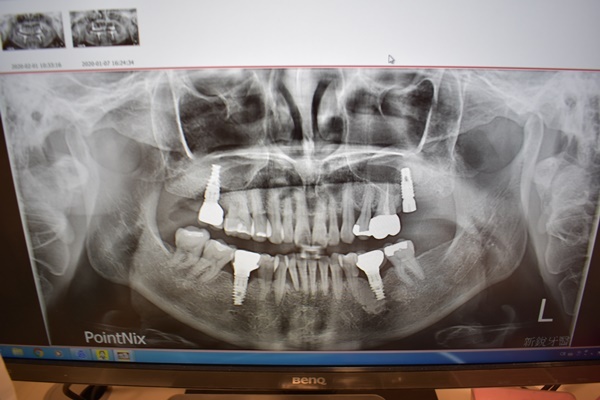

植牙手術時間是跟牙科敲11點,我們約莫早上10:40分左右就已經到達牙科,一到診所劉有恆醫師剛幫另一個病人做完植牙手術下樓,我媽則是劉醫師今天早上第二個微創植牙手術病人。

台中植牙醫師:劉有恆醫生 駐診院所:新銳牙醫診所

植牙手術前護士有先拿幾顆口服藥讓我媽服用,然後就跟我媽一起上到二樓植牙治療專用室,進到治療護士已經穿好手術服等著我媽,接著劉醫師到診間後拿著黃色消毒藥水將我媽嘴巴四周圍劃過一圈,本覺得很奇怪不是只有嘴巴要做手術嗎?怎麼連口腔兩側臉頰部分都要消毒?!後來才知道做微創植牙醫師很要求醫療衛生,大面積消毒才可以避免感染問題,消毒徹底才能打口內麻醉針。

一旁有個護士不停拿著吸水管在她嘴巴裡面游移吸走那些口水,為了要陪她做手術護士也請我換上跟醫師一樣的藍色手術衣跟帽子,都感覺自己變成植牙醫師一樣要幫她做手術,然後就看著護士幫她蓋上一塊綠色洞巾只露出嘴巴,劉有恆醫師動作很快地在牙齒位置四周圍又補了近六隻的麻醉藥。

動作很迅速拿著檯面上器械搬弄她的嘴唇執行著微創植牙,瞬間看到血淋淋畫面上演著,鑽開牙肉後些微的血絲,醫生還逗趣對著我說要我瞪大眼睛看一下,等下就可以看到薄薄的灰白色就是骨頭,接著拿起鑽子在骨頭上打洞鎖上很小的螺絲釘(貌似俗稱的植牙專用植體)

螺絲釘打好之後劉醫師就跟一旁護士說拿骨粉過來,用很細的鑷子拿起兩塊白色物狀塞到翻開的牙肉裡面,再使用像剪刀彎鉤的器械做傷口縫合,看到劉醫師這樣縫補傷口當下我心裡想這位醫師應該在家應該是負責縫補衣服吧!!手工了得~~~

微創植牙果然如傳說中快速還沒有十分鐘劉醫師就完成治療,護士接著拿著酒精棉布幫我媽把嘴巴四周圍藥水很用心擦拭過一遍,再拿微創植牙手術保養單仔細叮嚀我帶媽媽回家後要怎麼幫她做傷口保養,手術後48小時內臉部會紅腫冰敷盡量不要停….等等,離院前護士準備一個很可愛的牙齒冰敷袋&植牙漱口水可以帶回家,這次目睹我媽最微創植牙並沒有想像中來得恐怖,和拔智齒比較起來好像植牙容易簡單多啦!!